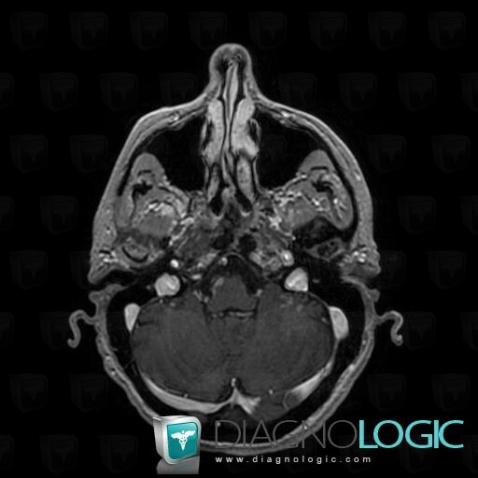

Les images ci-dessous illustrent ce dossier pour les diagnostics Carcinose méningée, Méningite carcinomateuse, pour les modalités (IRM)

Voici les informations spécifiques à l'image clé ci dessus:

- Diagnostic Méningite carcinomateuse, Localisation(s) Région cortico sous corticale, comportant les gammes Lésion sous corticale

Voici les informations spécifiques à l'image clé ci dessus:

- Diagnostic Méningite carcinomateuse, Localisation(s) Espaces peri cérébraux supratentoriels, comportant les gammes Réhaussement méningé focal, Lésion extra axiale supra tentorielleRégion cortico sous corticale, comportant les gammes Lésion sous corticale, Réhaussement méningé focal, Lésion corticale

Voici les informations spécifiques à l'image clé ci dessus:

- Diagnostic Méningite carcinomateuse, Localisation(s) Espaces peri cérébraux supratentoriels, comportant les gammes Réhaussement méningé focal, Lésion extra axiale supra tentorielleRégion cortico sous corticale, comportant les gammes Lésion sous corticale, Réhaussement méningé focal, Lésion corticale